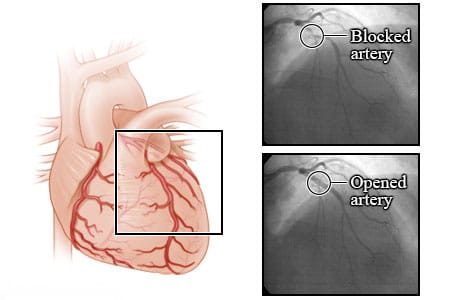

Coronary angioplasty

Coronary arteries are the blood vessels that supply oxygen-rich blood to the heart muscle. Coronary artery disease can cause plaque to build up inside the walls of the coronary arteries. Plaque is made up of extra cholesterol, calcium, and other substances that float in blood.

This plaque buildup may narrow the artery and reduce the blood flow to the heart muscle. This narrowing can cause angina symptoms such as chest pain or pressure. Sometimes the plaque can tear or rupture. The body tries to repair the tear by forming a blood clot over it. The blood clot can completely block blood flow and cause a heart attack. A procedure called angioplasty can widen a narrowed or blocked coronary artery.